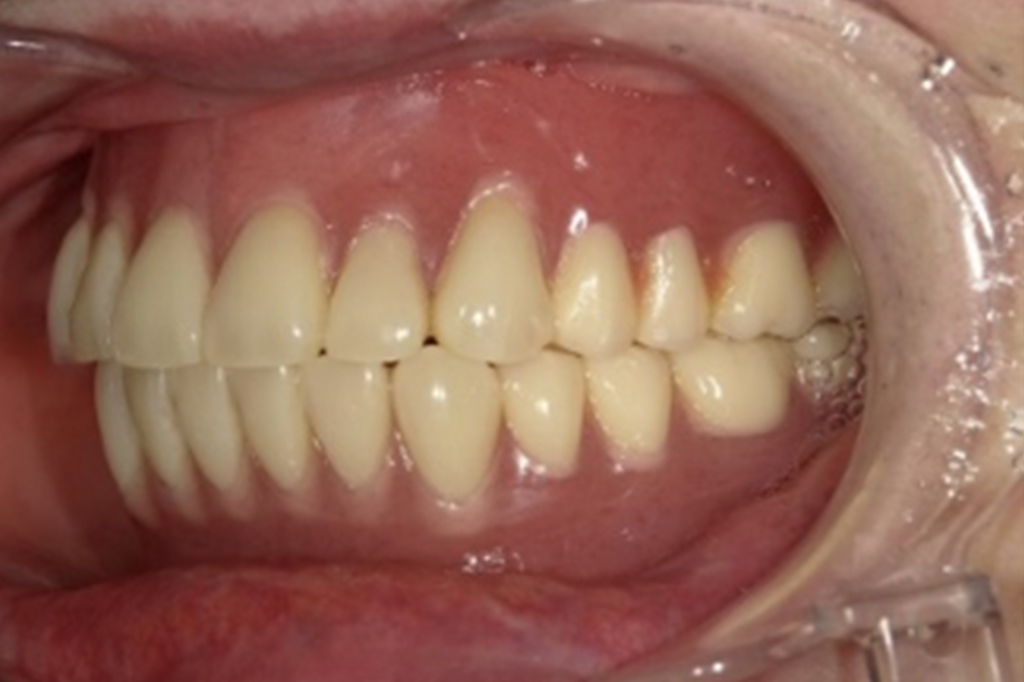

入れ歯の試適

• 兵庫県南あわじ市・医療法人 太田歯科・矯正歯科

完成前に入れ歯の適合試験を行います。

入れ歯が安定しているか、装着した際のお顔の表情・口元に歪が生じないかなど、生体と調和しているかどうかを確認します。